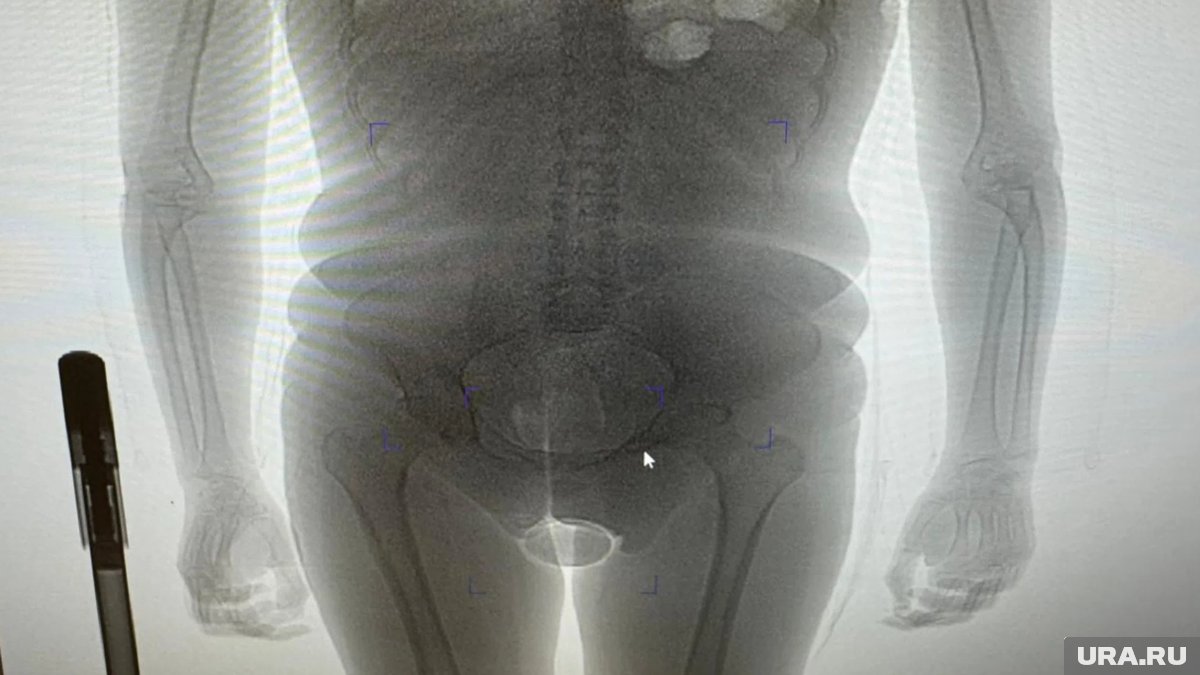

«В результате проведения таможенного досмотра обнаружено два презерватива с порошкообразным веществом внутри, один из которых находился в нижнем белье пассажирки, второй сокрыт внутриполостным способом», — говорится в заявлении пресс-секретаря. Информация есть в распоряжении URA.RU.

Девушка пояснила, что вещество представляет собой кокаин, который она согласилась перевезти по просьбе неустановленного мужчины за денежное вознаграждение. Проведенная экспертиза подтвердила, что изъятое вещество является кокаином общей массой 250 граммов. Сейчас иностранка заключена под стражу. В отношении нее возбуждено уголовное дело по статье о контрабанде наркотических средств в особо крупном размере. Санкция данной статьи предусматривает лишение свободы на срок от 15 лет до пожизненного заключения с возможным штрафом до одного миллиона рублей.